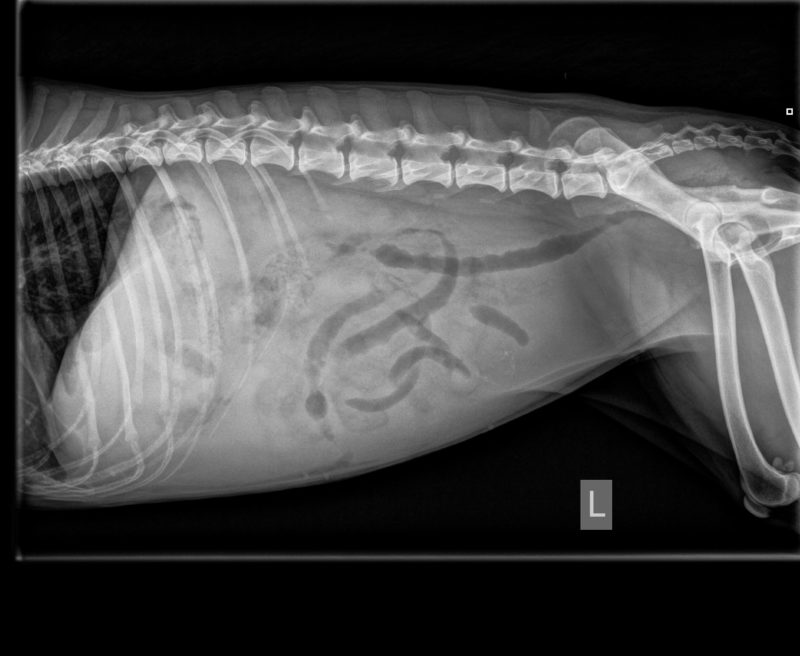

Als erste Diagnostik wurde der Hündin Blut abgenommen, um einen Blutstatus (u.a. rote und weiße Blutkörperchen, Hämatokrit, etc.) zu erstellen. In der Zwischenzeit wurde ein Röntgenbild des Abdomens erstellt. Auf dem Röntgenbild war eine hochgradige Aszites (Flüssigkeitsansammlung in der Bauchhöhle) zu sehen, daher war das Abdomen nicht wirklich beurteilbar und aufgrund dessen wurde ein Ultraschall angesetzt. Hier zeigte sich, dass die Blase geringgradig Urinsediment aufwies, die Nieren sowie die Milz waren makroskopisch unauffällig, die Leber war deutlich verkleinert und inhomogen, die Gallenblasenwand erschien geringgradig verdickt. Die Dünndarmschlingen waren etwas hyperechogen und zeigten eine verdickte Mukosa, bei erhaltener Darmschichtung. Es erfolgte eine ultraschallgeführte Punktion der Bauchhöhle, um ein Probe der Bauchhöhlenflüssigkeit zu bekommen. Diese war makroskopisch wie Wasser ohne Hinweise auf Blutbeimengungen oder einem besonderem Geruch.